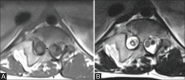

Spinal cord development occurs through three consecutive periods of gastrulation, primary nerulation and secondary neurulation. Aberration in these stages causes abnormalities of the spine and spinal cord, collectively referred as spinal dysraphism. They can be broadly classified as anomalies of gastrulation (disorders of notochord formation and of integration); anomalies of primary neurulation (premature dysjunction and nondysjunction); combined anomalies of gastrulation and primary neurulation and anomalies of secondary neurulation. Correlation with clinical and embryological data and common imaging findings provides an organized approach in their diagnosis.